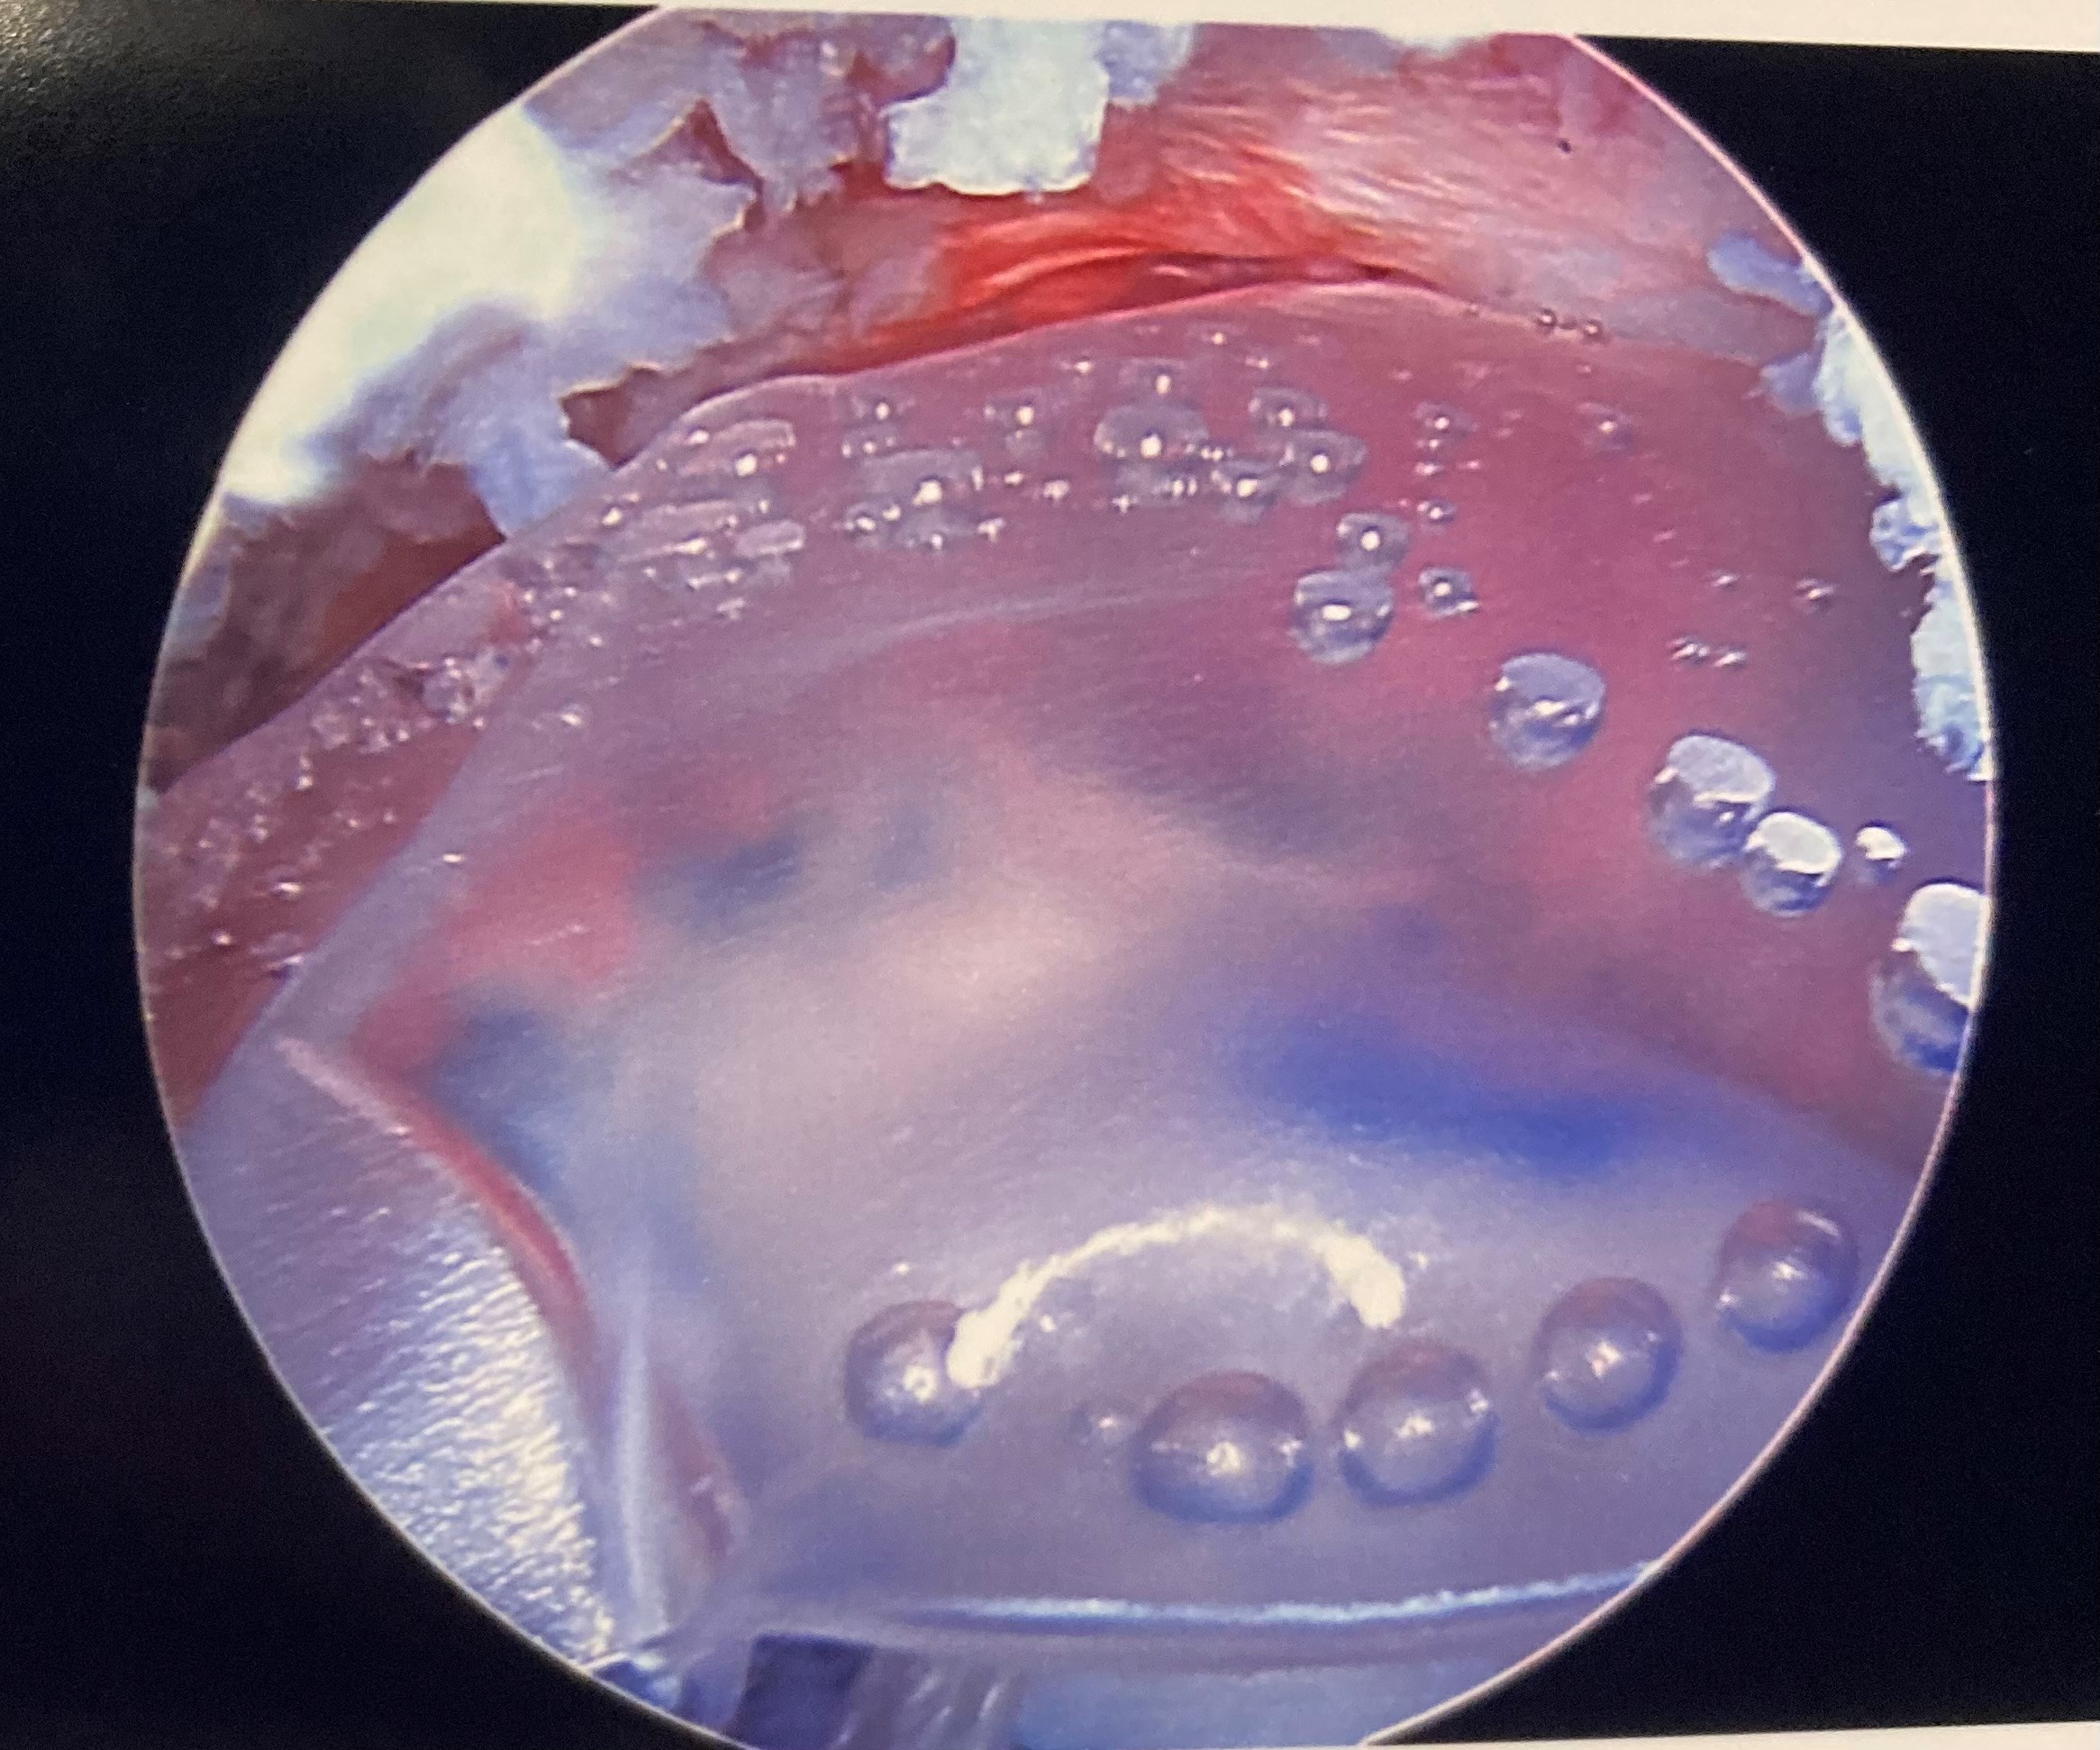

When performing a subacromial balloon spacer technique, the surgeon first clears and prepares the area around the rotator cuff tear. The surgeon then inflates a small balloon, between the humeral head — the top of the humerus that fits into the shoulder joint — and the roof acromion, above the shoulder joint.

The space created by the balloon between the humeral head and the acromion, which is the bony tip of the outer edge of the shoulder blade, is the key to pain relief for patients with massive rotator cuff tears. The balloon acts as a natural barrier between the humeral head and the acromion, pushing lightly down on the humeral head to avoid contact with the acromion. Otherwise, when patients lift their shoulder, the humeral head pinches on the roof, which may cause significant pain.

balloon orthoThe balloon spacer cushions bone-on-bone impacts in severe cases of rotator cuff injury.After the balloon spacer procedure, patients can safely rehabilitate their shoulder through physical therapy. Eventually, the balloon will dissolve. Many patients still report pain relief even after the balloon dissolves, possibly due to the effects of quality physical therapy sessions while the balloon was in place.